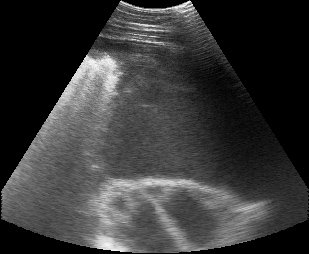

pleuropolmonite 2